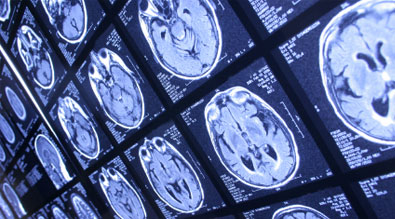

Angiogram shows a large AVM of the parietal lobe in a patient presenting with seizures central vision, and is the cause of her complaint. 3:42. 33. back pain neck slip & fall pain headaches car accidents auto relief massage therapy vancouver washington chiropractor ... View Video